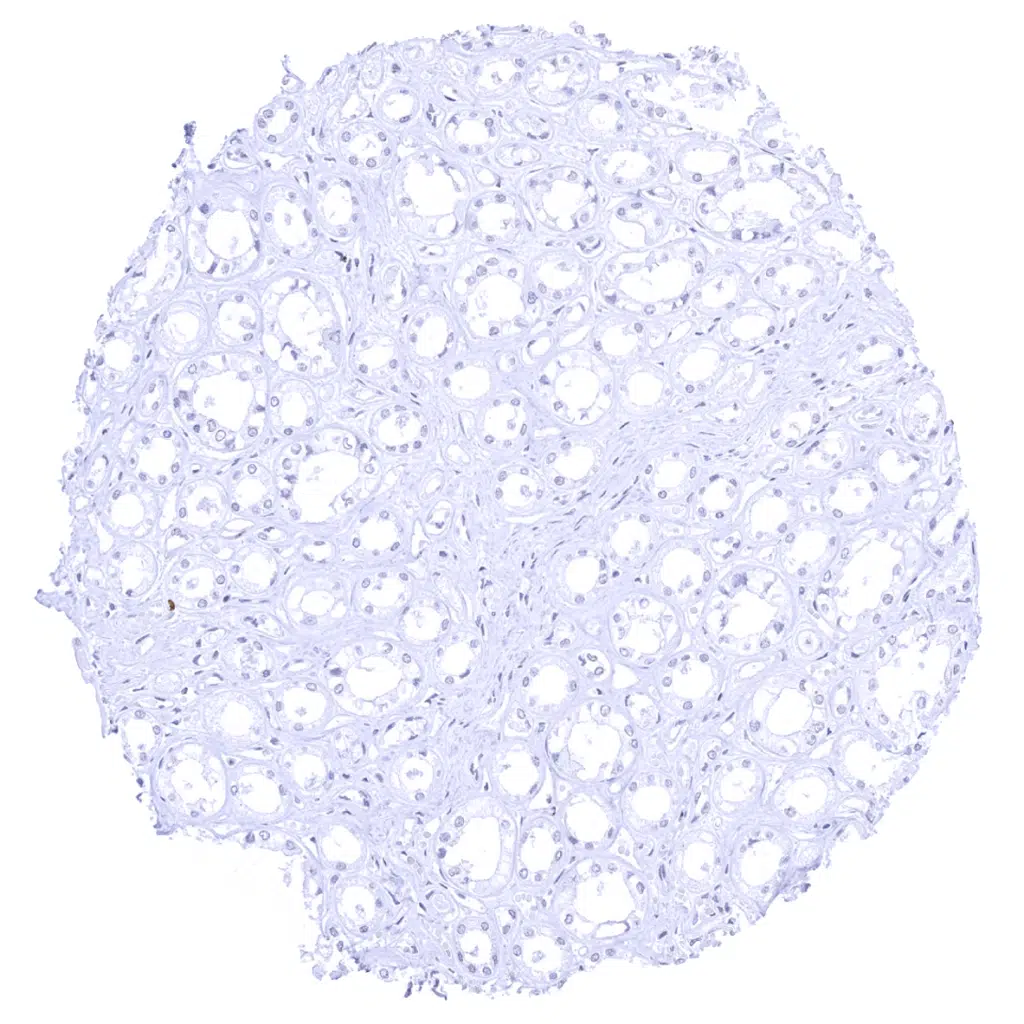

Testis